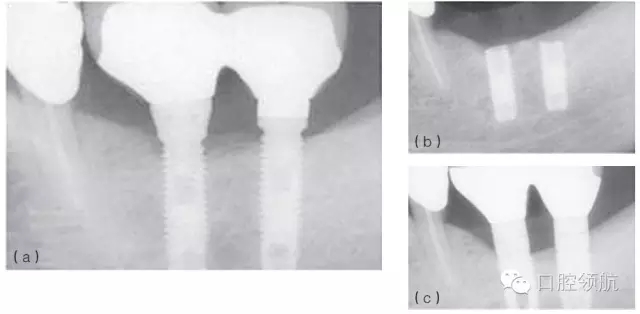

例如,在發(fā)生率低的種植體折斷病例中,感染和創(chuàng)傷經(jīng)常同時(shí)存在,或相繼發(fā)生。感染引起的種植體周骨喪失(種植體周圍炎)也可能導(dǎo)致種植體折斷。過載或創(chuàng)傷則是種植體折斷的第二個因素,種植體折斷的高度常常與骨-種植體的接觸水平相一致(圖6.4a~c)。也可相反,種植體周感染繼發(fā)于咬合創(chuàng)傷,導(dǎo)致種植體不能形成骨結(jié)合而失敗。(圖6.5a~c)

圖6.4 (a)18號、19號位點(diǎn)種植體出現(xiàn)邊緣骨吸收。(b)2年后出現(xiàn)折斷。(c)拔除了舊的種植體,新的種植體植入并進(jìn)行修復(fù)。

圖6.5 (a)不正確咬合引起的側(cè)向力導(dǎo)致過度負(fù)荷。(b)種植體周圍感染伴發(fā)骨結(jié)合喪失。(c)重新植入種植體并恢復(fù)正確的咬合。